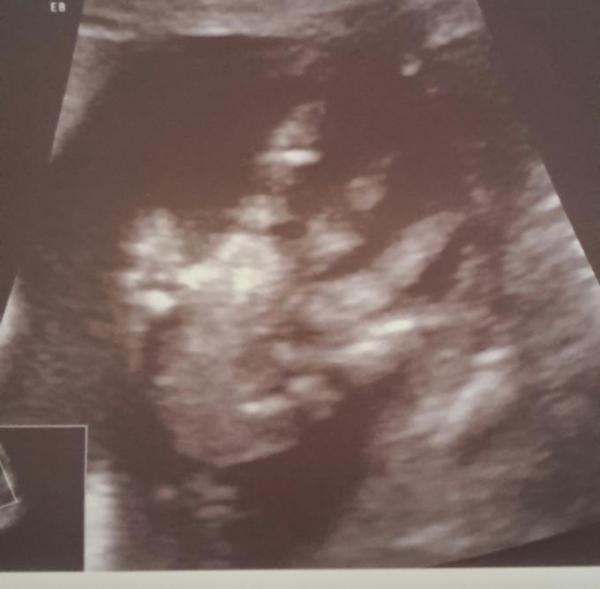

Wir hatten heute unseren 3d Termin und es war kaum möglich das hyperaktive Kind einzufangen ständig Hände vor dem Gesicht oder weg gedreht usw. Vermessen wurde er dann auch und wir sind zwei Wochen voraus sprich ich müsste eigentlich in den Juli wechseln aber mag ich gar nicht Anbei eine kleine winkehand

Bild zu Darf ich trotzdem bleiben? :-D - Forum für August - Mamis